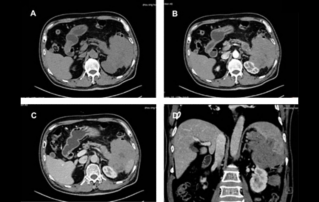

Female pelvic floor anatomy, which developed since the early 20th century, has had a variety of theories, including integral theory, three levels of vaginal support theory, "hammock hypothesis", and three-chamber system. Supporting structures such as pelvic floor muscles, fascia and ligament play an important role in maintaining the normal function of pelvic floor, among which levator ani muscle group is one of the most important supporting structures.